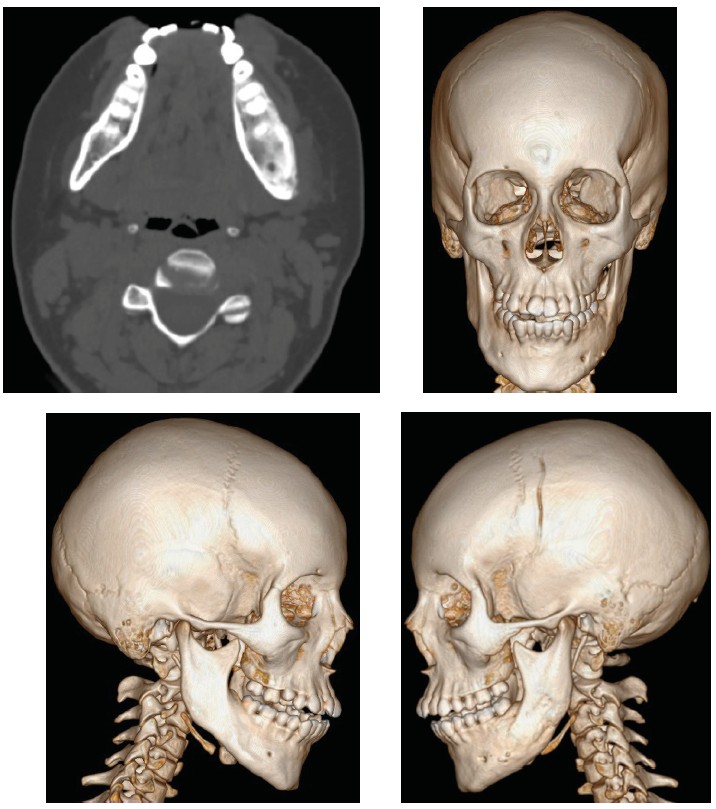

Throughout the subsequent year, no relapses were observed; however, in the month prior to the second admission which was in April 2022, the patient experienced mild pain on the right side of the lower jaw, necessitating readmission to the RDKB. A MSCT scan conducted upon admission revealed a softening focus measuring up to 5 mm in depth and 1 cm in diameter located at the angle of the right half of the lower jaw, accompanied by a cystic cavity in the vicinity of the roots of tooth 3.5. Additionally, an irregular structure of the body of the left half of the lower jaw was noted (Figure 3).

Fig. 3. MSCT scan in April 2022 exhibits the extension of the bone destruction on both halves of the mandible